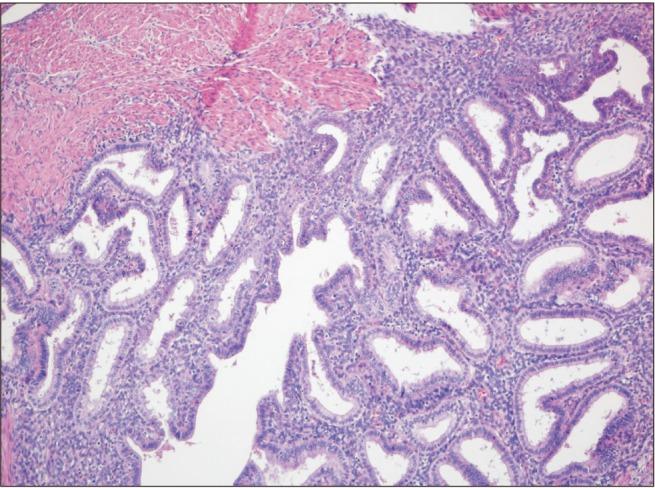

Endometriosis is a benign gynecologic disease that highly influences women of childbearing age. It is characterized by ectopic endometrial tissue. Primary umbilical endometriosis is a rare condition. It is a benign disease with endometrial tissue in an abnormal site in the navel. It may be accompanied with pain in the navel and a discolored bump. Among all locations with the potential for endometriosis, the navel has less than 1% incidence of primary umbilical endometriosis. In the present study, we reported a rare case of umbilical endometriosis revealed via a biopsy performed for a 49-year-old menopausal woman with the complaint of pain in the navel who underwent surgical excision and a biopsy after a scan.

子宫内膜异位症是一种对育龄女性影响极大的良性妇科疾病。其特征为异位的子宫内膜组织。原发性脐部子宫内膜异位症是一种罕见病症。它是一种良性疾病,在肚脐这个异常部位存在子宫内膜组织。可能伴有肚脐疼痛和变色肿块。在所有可能发生子宫内膜异位症的部位中,原发性脐部子宫内膜异位症的发病率低于1%。在本研究中,我们报告了一例罕见的脐部子宫内膜异位症病例,该病例是通过对一名49岁绝经女性进行活检发现的,该女性因肚脐疼痛前来就诊,在扫描后接受了手术切除及活检。